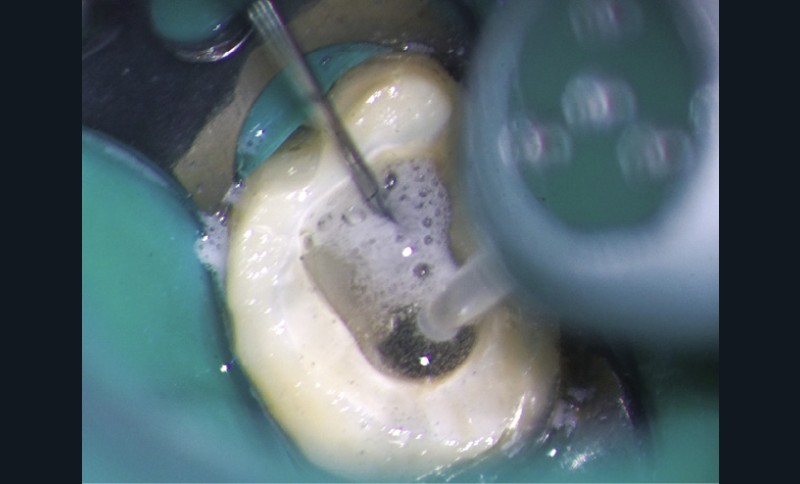

Le laser Er:YAG va permettre une élimination des débris en surface, une stérilisation, avec comme irrigation de l’eau stérile [36] et en coupant le spray, une hémostase avec la formation d’une couche de coagulation [37] propre à la formation d’un pont dentinaire au contact du biomatériau, qui peut être bio-actif, tel que la Biodentine (Septodont) (fig. 6a à d).

Protocole opératoire : sous anesthésie, une cavité suffisante à recevoir le biomatériau (2 à 3 mm) sous champ opératoire est réalisée. La désinfection au laser Er:YAG (40 mJ ; 20 Hz) sous spray, pendant 20 secondes, est alors mise en œuvre. S’en suit éventuellement une coagulation de 3 secondes, en coupant le spray, puis la mise en place du biomatériau Biodentine (Septodont). Il sera ensuite recouvert d’un matériau de restauration adéquate.